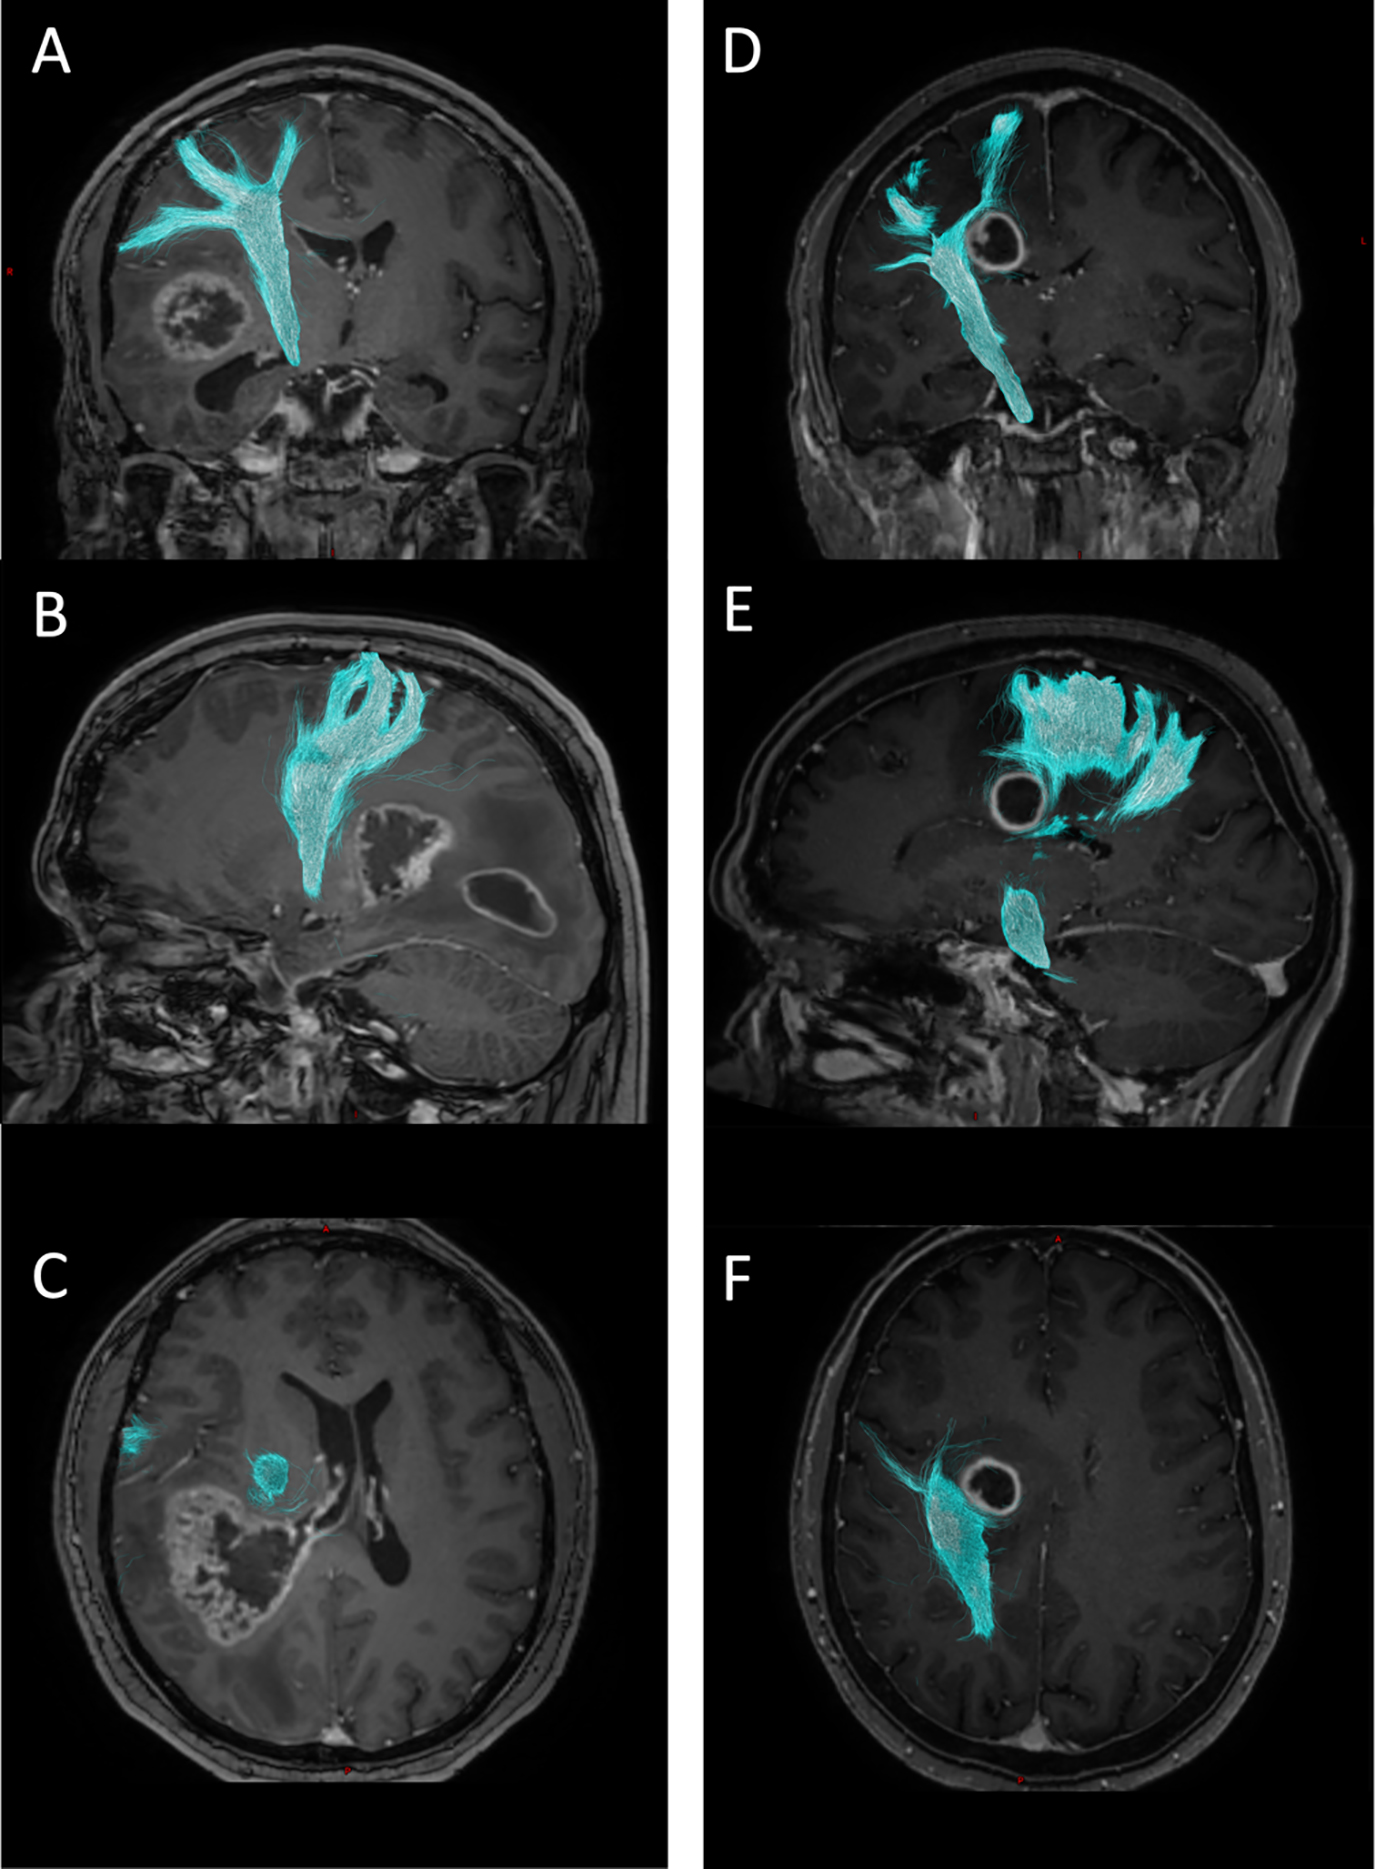

Fig. 1.Example tractograms of the right CST (cyan). Preoperative contrast-enhanced T1-weighted MPRAGE sequence. (A–C) 34-year-old male patient with multifocal glioblastoma WHO grade 4 in the right hemisphere. NPS preoperative 2, postoperative 4. Preoperative median FA of the right CST 0.3972. (D–F) 62-year-old female patient with glioblastoma WHO grade 4 in the right hemisphere. NPS preoperative 2, postoperative 1. Preoperative median FA of the right CST 0.2706.